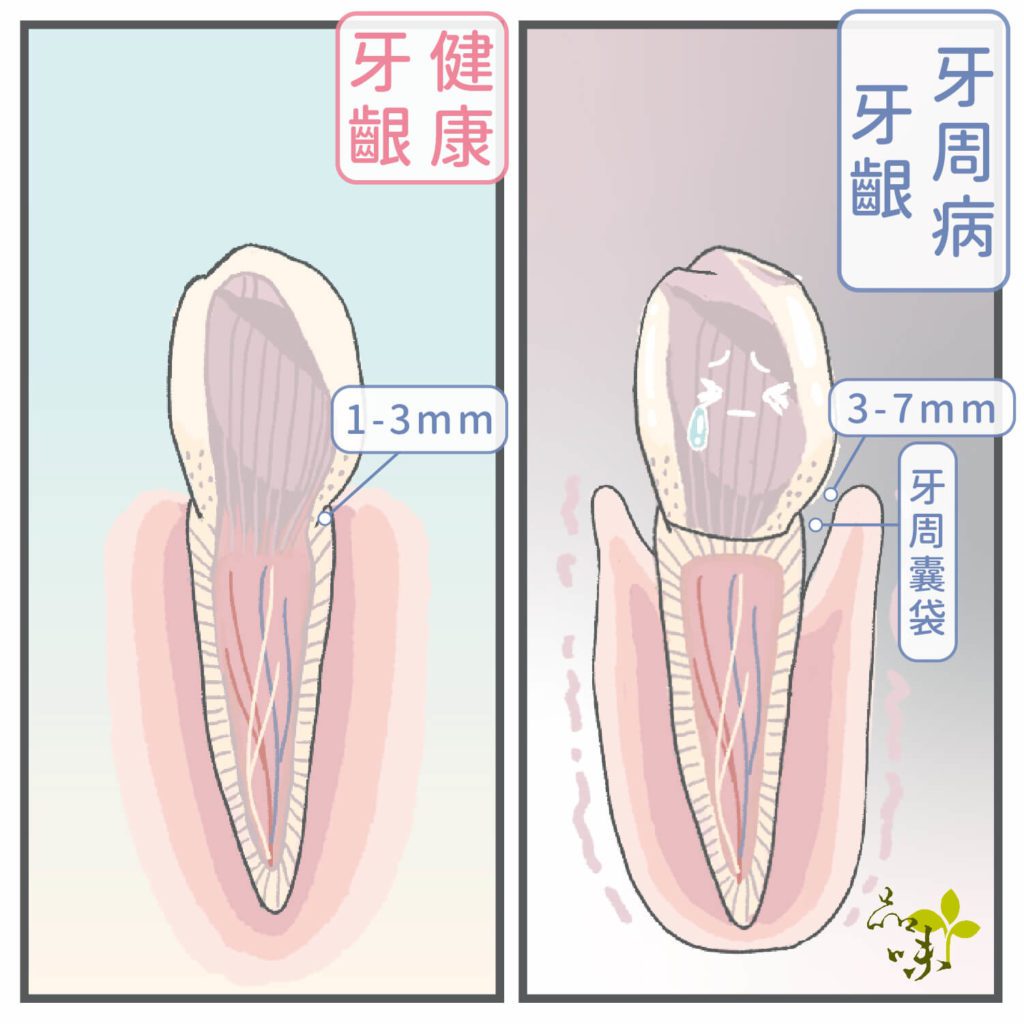

1. 牙周病:

牙齦和牙齒間的牙結石長期堆積,會造成牙周囊袋變得更難清潔,進一步地侵蝕齒槽骨,骨質流失後,導致牙齦嚴重退縮。

如果是嚴重牙周病,更可能使牙齒開始動搖,通常這種情況的牙齦萎縮做任何手術都是沒有用的。